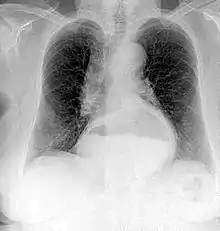

Projectional radiographs

Projectional radiography is the practice of producing two-dimensional images using X-ray radiation. Bones contain a high concentration of calcium, which, due to its relatively high atomic number, absorbs X-rays efficiently. This reduces the amount of X-rays reaching the detector in the shadow of the bones, making them clearly visible on the radiograph. The lungs and trapped gas also show up clearly because of lower absorption compared to tissue, while differences between tissue types are harder to see.

Projectional radiographs are useful in the detection of pathology of the skeletal system as well as for detecting some disease processes in soft tissue. Some notable examples are the very common chest X-ray, which can be used to identify lung diseases such as pneumonia, lung cancer, or pulmonary edema, and the abdominal x-ray, which can detect bowel (or intestinal) obstruction, free air (from visceral perforations), and free fluid (in ascites). X-rays may also be used to detect pathology such as gallstones (which are rarely radiopaque) or kidney stones which are often (but not always) visible. Traditional plain X-rays are less useful in the imaging of soft tissues such as the brain or muscle. One area where projectional radiographs are used extensively is in evaluating how an orthopedic implant, such as a knee, hip or shoulder replacement, is situated in the body with respect to the surrounding bone. This can be assessed in two dimensions from plain radiographs, or it can be assessed in three dimensions if a technique called '2D to 3D registration' is used. This technique purportedly negates projection errors associated with evaluating implant position from plain radiographs.[104]